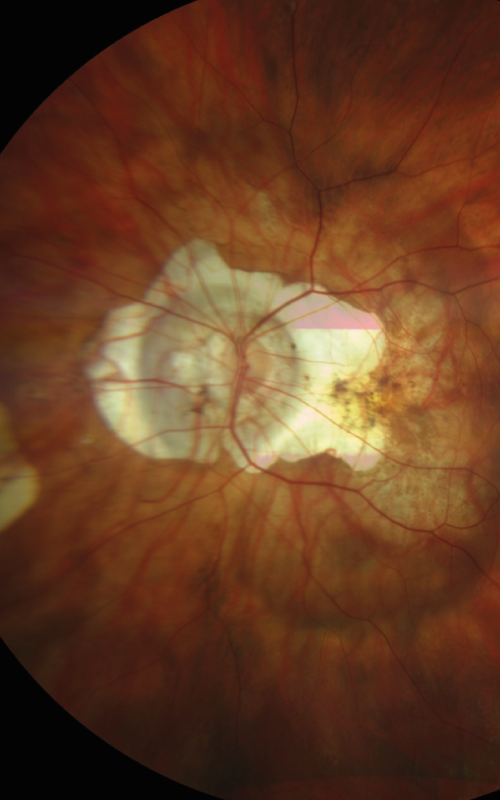

Cas Clinique – quand une CRSC se complique…

Ce cas illustre la complexité du spectre des pachychoroïdes et rappelle que toute CRSC atypique ou persistante doit faire rechercher une néovascularisation associée. L’imagerie multimodale est ici essentielle pour affiner le diagnostic et orienter la prise en charge.